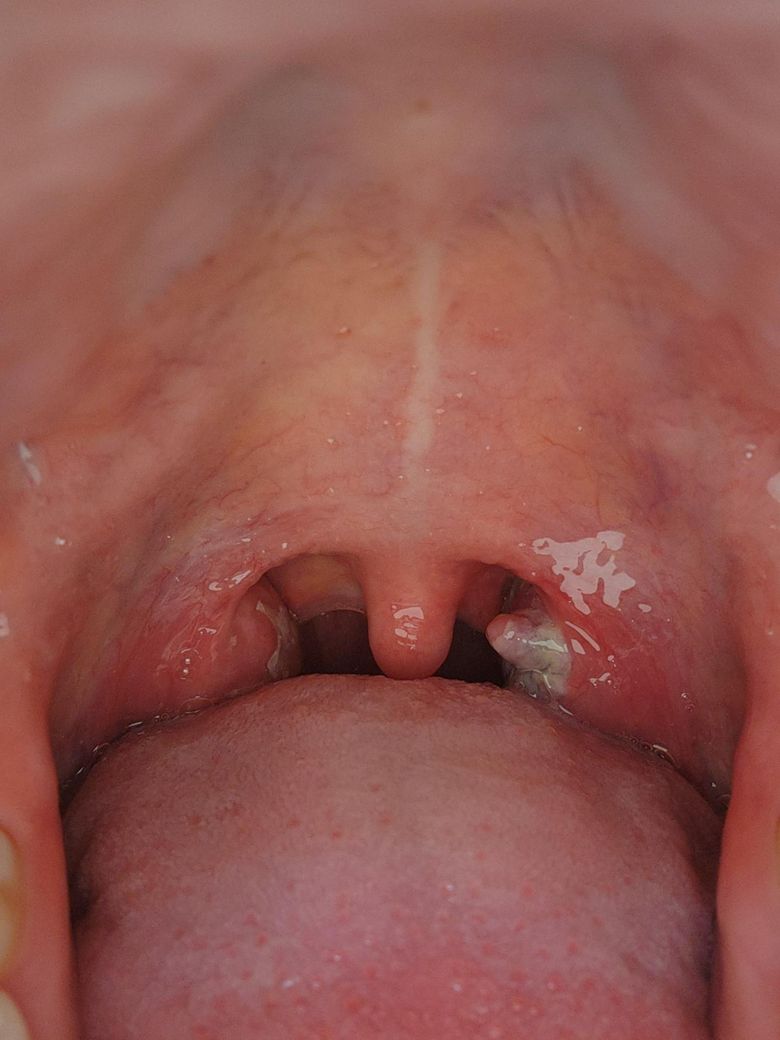

편도에 혹같은게 생겼어요 봐주세요ㅠㅠ

저번주 화욜부터 열이나고 목이아팠는데 일때문에 금요일에 병원가니까 편도염이라고하더라구요 편도에 하얀게 묻어있었어요 다음주가 설이라서 약을 일주일치를 받았는데

오늘 보니까 편도에 혹같은게 또 생긴거같아여 저번주는 없었는데ㅠㅠ 혹도 편도염의 일종인가여 응급실같은데 가야하나요? 열은 거의안납니다

사진상 좌측 편도에 국소적으로 돌출된 병변과 황백색 분비물이 관찰됩니다. 최근 발열과 인후통 병력이 있고 항생제 치료 중이라면, 급성 편도염 경과 중 발생한 염증성 부종 또는 국소 농양 형성(편도주위 농양 초기 단계) 가능성을 우선 고려합니다. 단순한 삼출성 편도염에서도 일시적으로 덩어리처럼 보일 수 있습니다.

현재 열이 거의 없고, 입 벌리기 어려움(개구장애), 침 삼키기 힘들 정도의 통증, 침 흘림, 한쪽으로 목젖이 심하게 밀려 보이는 소견, 말이 어눌해지는 증상(핫포테이토 보이스)이 없다면 즉시 응급실로 갈 상황은 아닐 가능성이 높습니다. 다만 통증이 한쪽으로 점점 심해지거나, 삼킴 곤란이 악화되면 당일 이비인후과 재내원 또는 응급 평가가 필요합니다.

현재로서는 처방받은 약을 규칙적으로 복용하면서 수분 섭취 유지, 경과 관찰이 적절해 보입니다. 가능하다면 1–2일 내 외래에서 직접 인후 진찰을 다시 받는 것이 안전합니다.